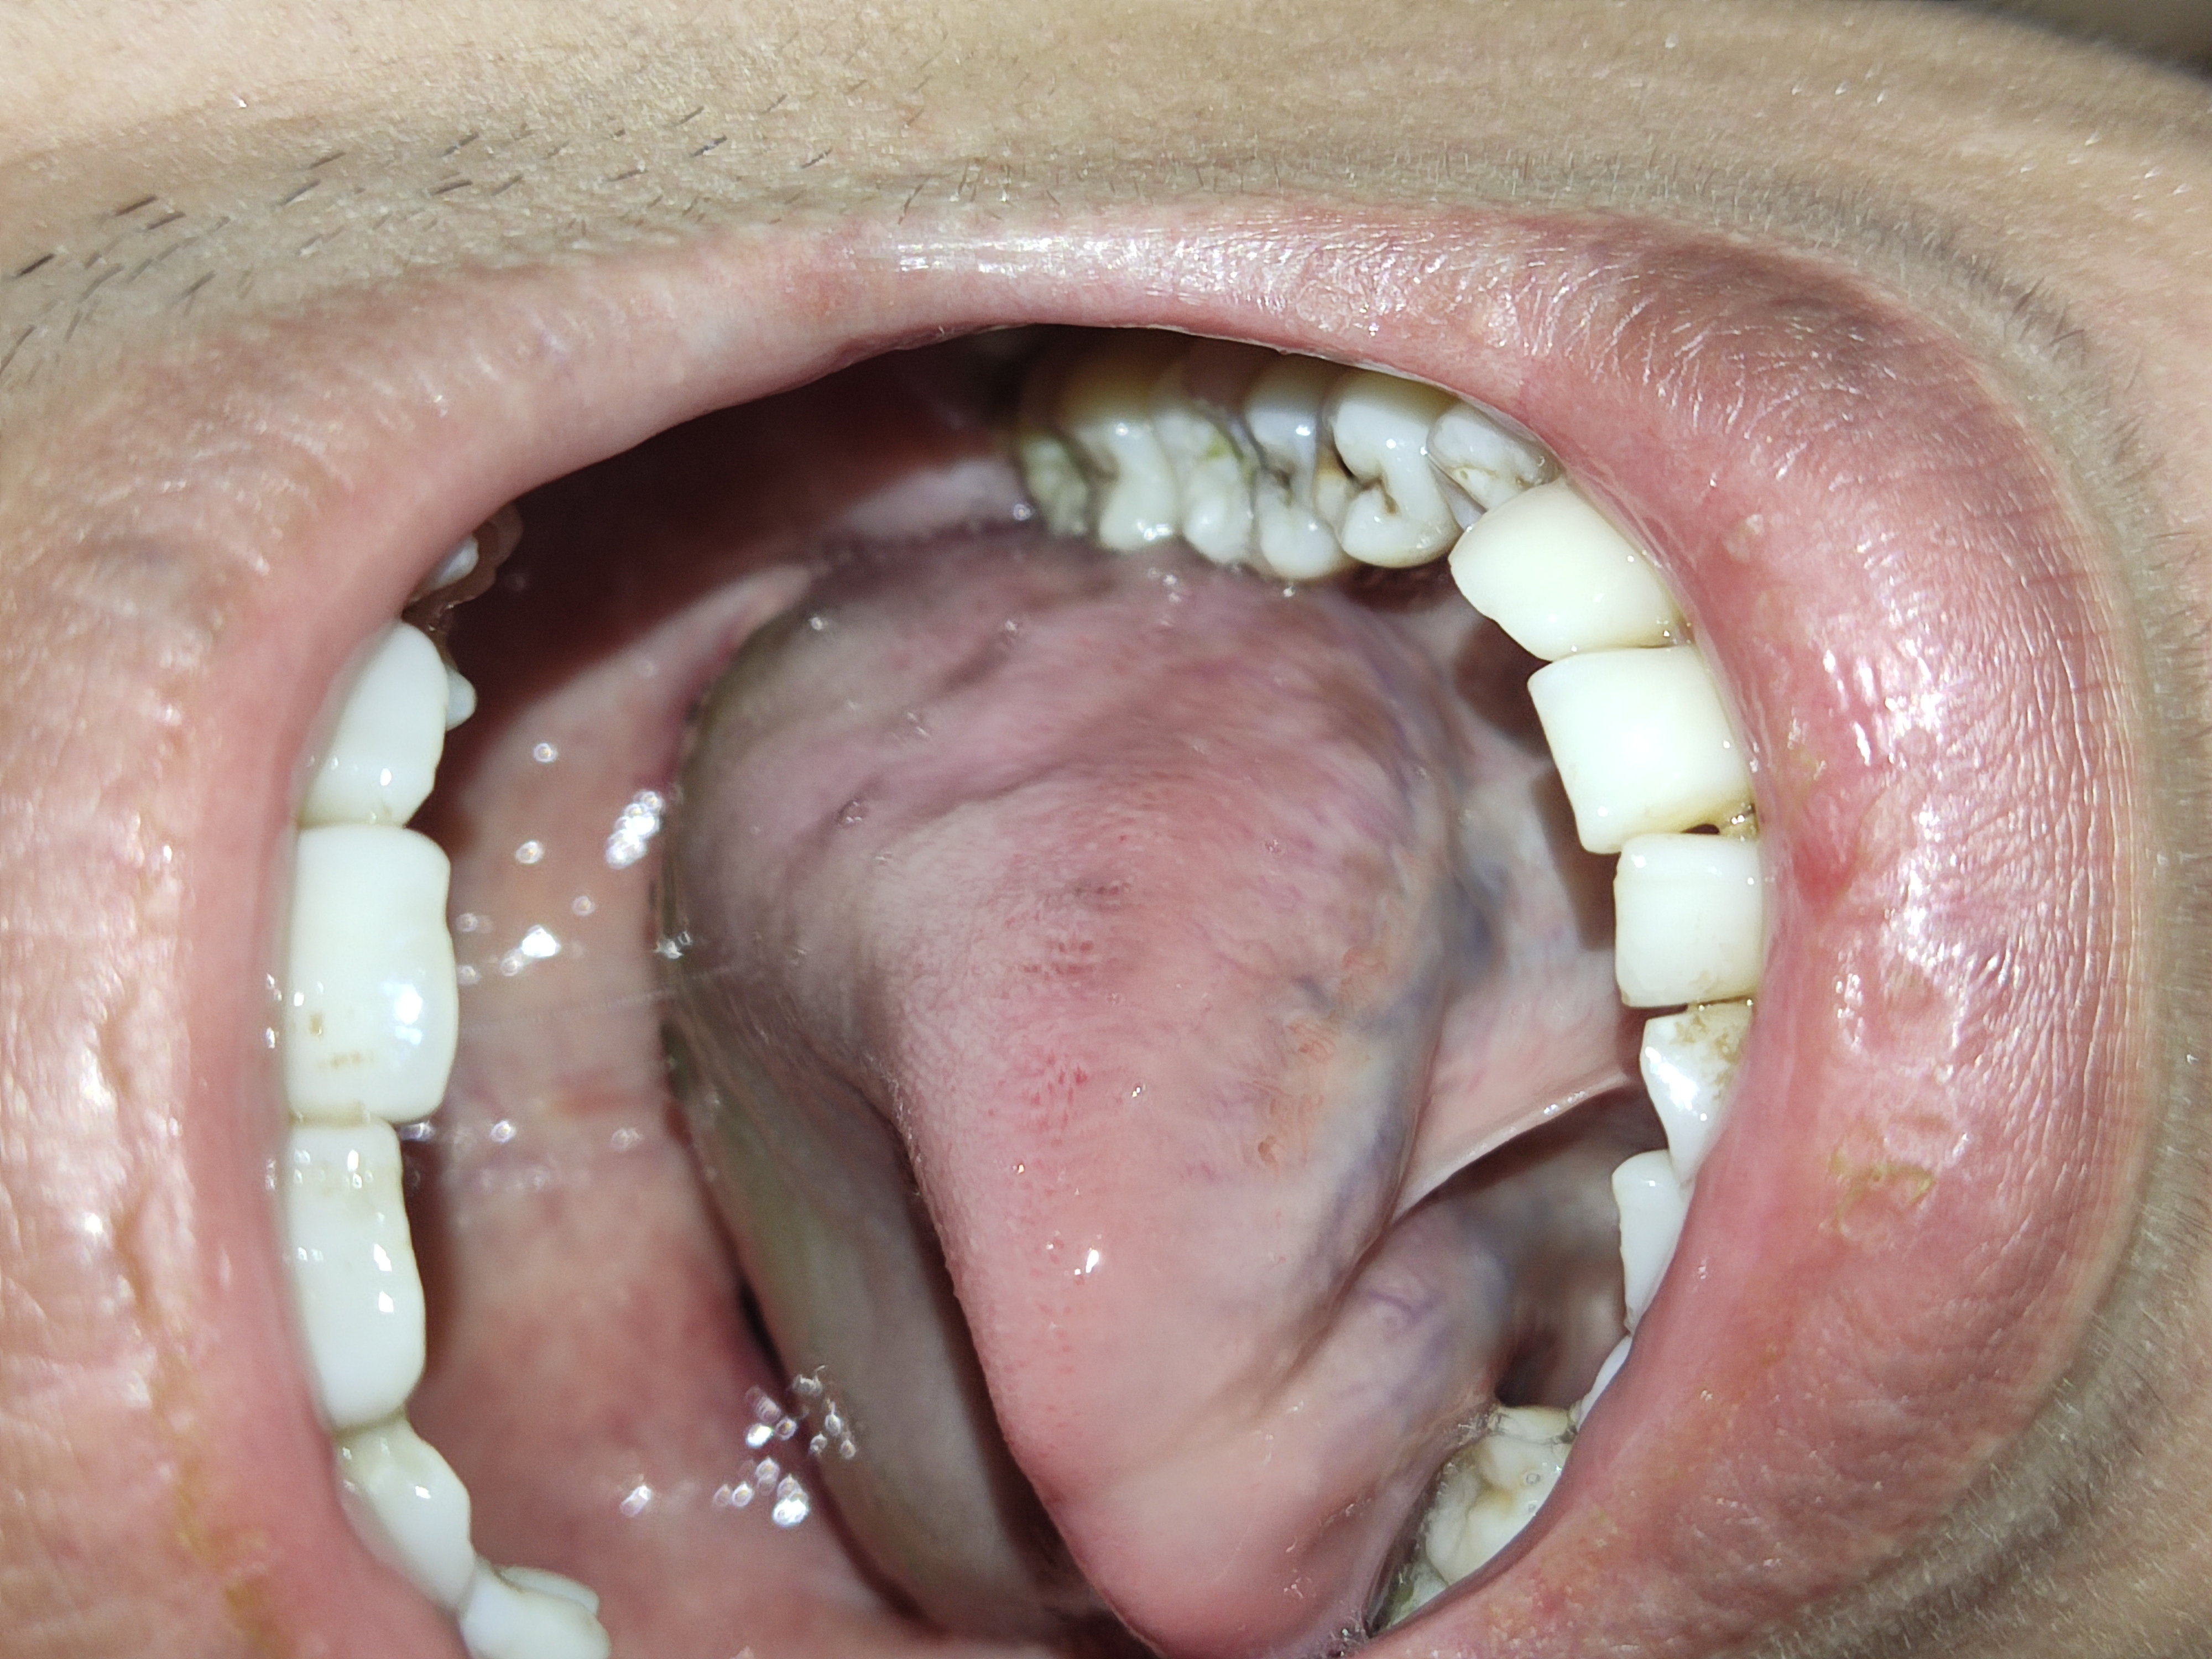

Lưỡi bị trắng

Bắc sĩ Cho em hỏi lưỡi em bị trắng vậy có sao không ạ

Chào em. Lưỡi trắng cần kiểm tra có viêm nhiễm xung quanh như viêm hầu họng hay không. Hoặc viêm nhiễm ở cơ quan khác